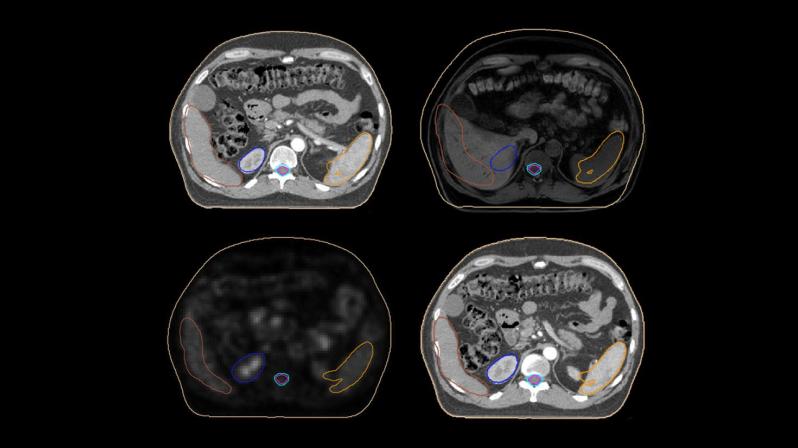

De acordo com Lina Vieira, docente da ESTeSL e coordenadora do BIP AMELY, este programa “pretende proporcionar uma oportunidade para os estudantes de licenciatura aprenderem e compreenderem os princípios, métodos e técnicas fundamentais envolvidos no processamento e avaliação da imagem médica. Assim, vão ser exploradas questões como os parâmetros de aquisição, algoritmos de reconstrução e métodos de segmentação, bem como, estes afetam a qualidade da imagem em diferentes contextos.”